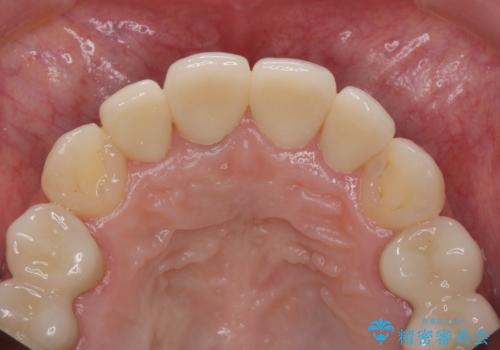

虫歯だらけの前歯をセラミック治療

- 52.8万円(ジルコニアクラウン×4・仮歯×4)費用は治療当時の料金となります

自然な歯の仕上がりに大変満足いただくことができました。